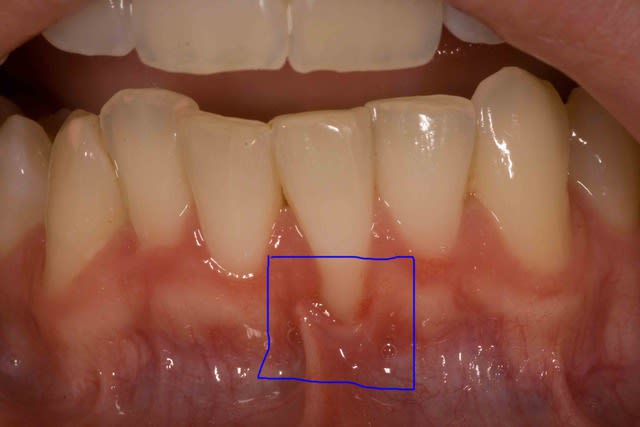

Je me permets de poursuivre ce post car j'ai un échec partiel sur lequel je m'interroge. Est-ce lié à la vestibulisation de l'incisive ? Devrais-je tenter un lambeau déplacé coronairement ?

Reste à faire un lambeau déplacé coronairement.

Sinon, je pense que les sutures auraient pu être différentes, et le greffon placer un peu plus haut.

dudule.. tu as recouvert à la hauteur que tu avais mis ton greffon.. ligne rejoignant gencive 33-43.

D'accord avec céramik, lambeau plus haut et sutures différentes.... mais comment? beaucoup de sutures peuvent nuire à la perfusion du greffon.

Ne pas oublier dent buccalée devient une Cl III de Miller, donc difficile de faire recouvrement complet...